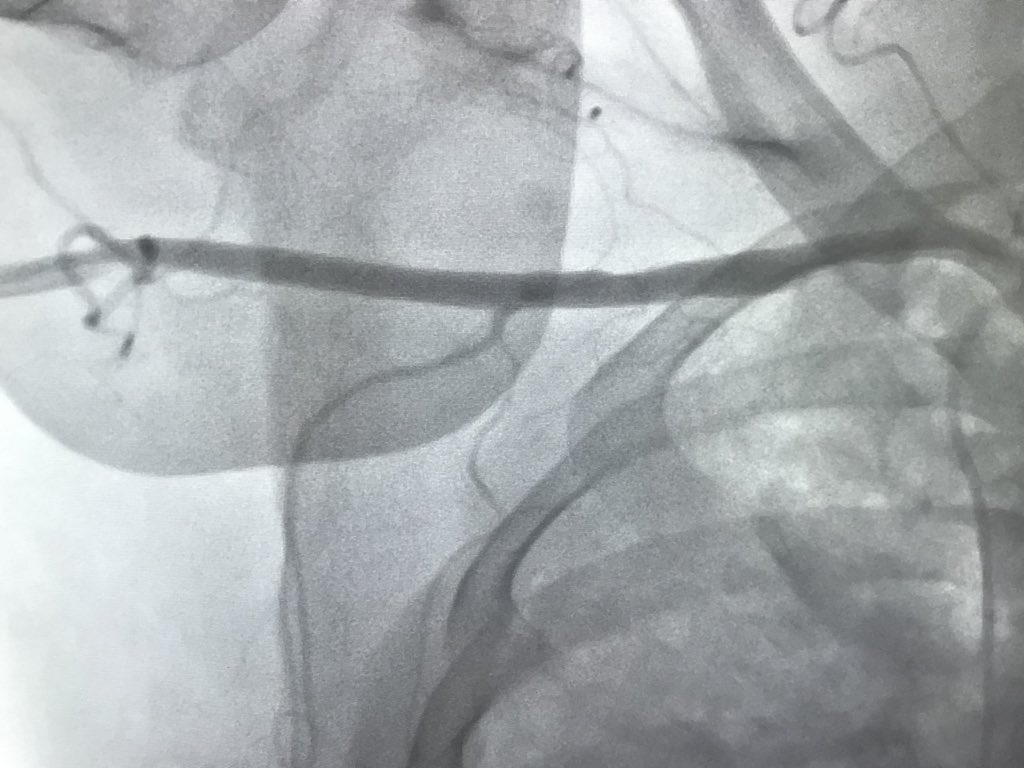

Then went #PercAx for heavily calcified LM in cardiogenic shock after we were unable to get catheters up from right and left radial, right femoral…and finding this gem in the left iliac

RajTayalMD's tweet image. Then went #PercAx for heavily calcified LM in cardiogenic shock after we were unable to get catheters up from right and left radial, right femoral…and finding this gem in the left iliac